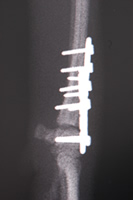

犬の撓側手根骨の脱臼の外科治療

1)、右の橈側手根骨の脱臼と思われました。

2)、3)、3D―CTで見てみますと橈側手根骨が内頭側へ脱臼しているのがはっきり分かりました。

4)、5)、橈側手根骨の整復の後、関節軟骨を除去し、更に腸骨より海綿骨を採取し、手根関節部に自家移植し、橈骨遠位と橈側手根骨を正面と内側斜面からプレートとスクリュー固定しました。

術後、二か月が経過しましたが、今では普通の生活をしています。